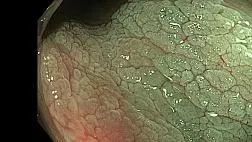

Главная Статьи Доброкачественные образования пищевода: эндоскопическая и морфологическая диагностика. Англ.версия

Статьи: Доброкачественные образования пищевода: эндоскопическая и морфологическая диагностика. Англ.версия